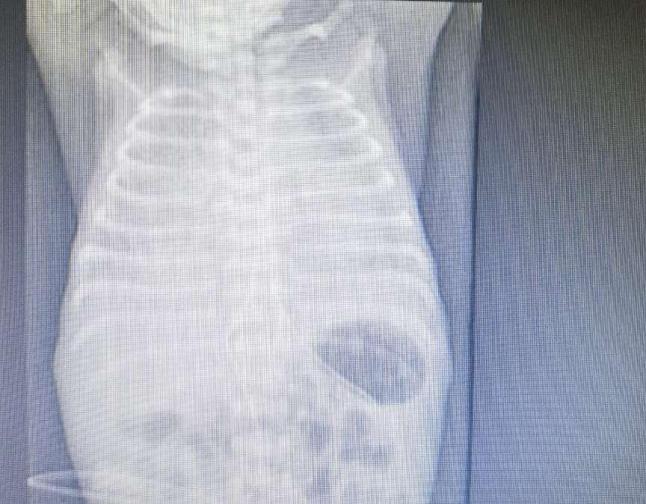

1月23日,当所有的人在欢度新春佳节时,王先生陪同怀孕27周的爱人来长沙走亲戚,结果爱人出现早产症状,提前在省妇幼分娩了。孩子胎龄小,生后出现呼吸困难,入住新生儿科。随后拍了胸片,医师告诉他孩子出现白肺,需要呼吸机来帮助通气,不然呼吸会很困难,甚至有生命危险。

早产儿早期的白肺,是因为肺发育不成熟,其肺表面活性物质不足导致进行性肺不张,生后数小时内气促等呼吸困难进行性加重,医学上称新生儿呼吸窘迫综合。该病一般多见于胎龄小于32周的早产儿。另外,如果孕母患妊娠期糖尿病、未发作行择期剖宫产、围产期窒息缺氧、重度血型不合溶血病、先天性基因缺陷等情况时,也会发病。

彭湘莲表示,白肺患者是新生儿重症监护病房的危急重症,往往需要气管插管,用呼吸机来帮助通气。随着NICU诊治能力的提高,经积极治疗,配合适宜的早产儿系统管理和监护后,多数患儿呼吸困难逐步缓解,呼吸机逐渐撤离。

(宝宝肺部治疗前和治疗后的照片。)